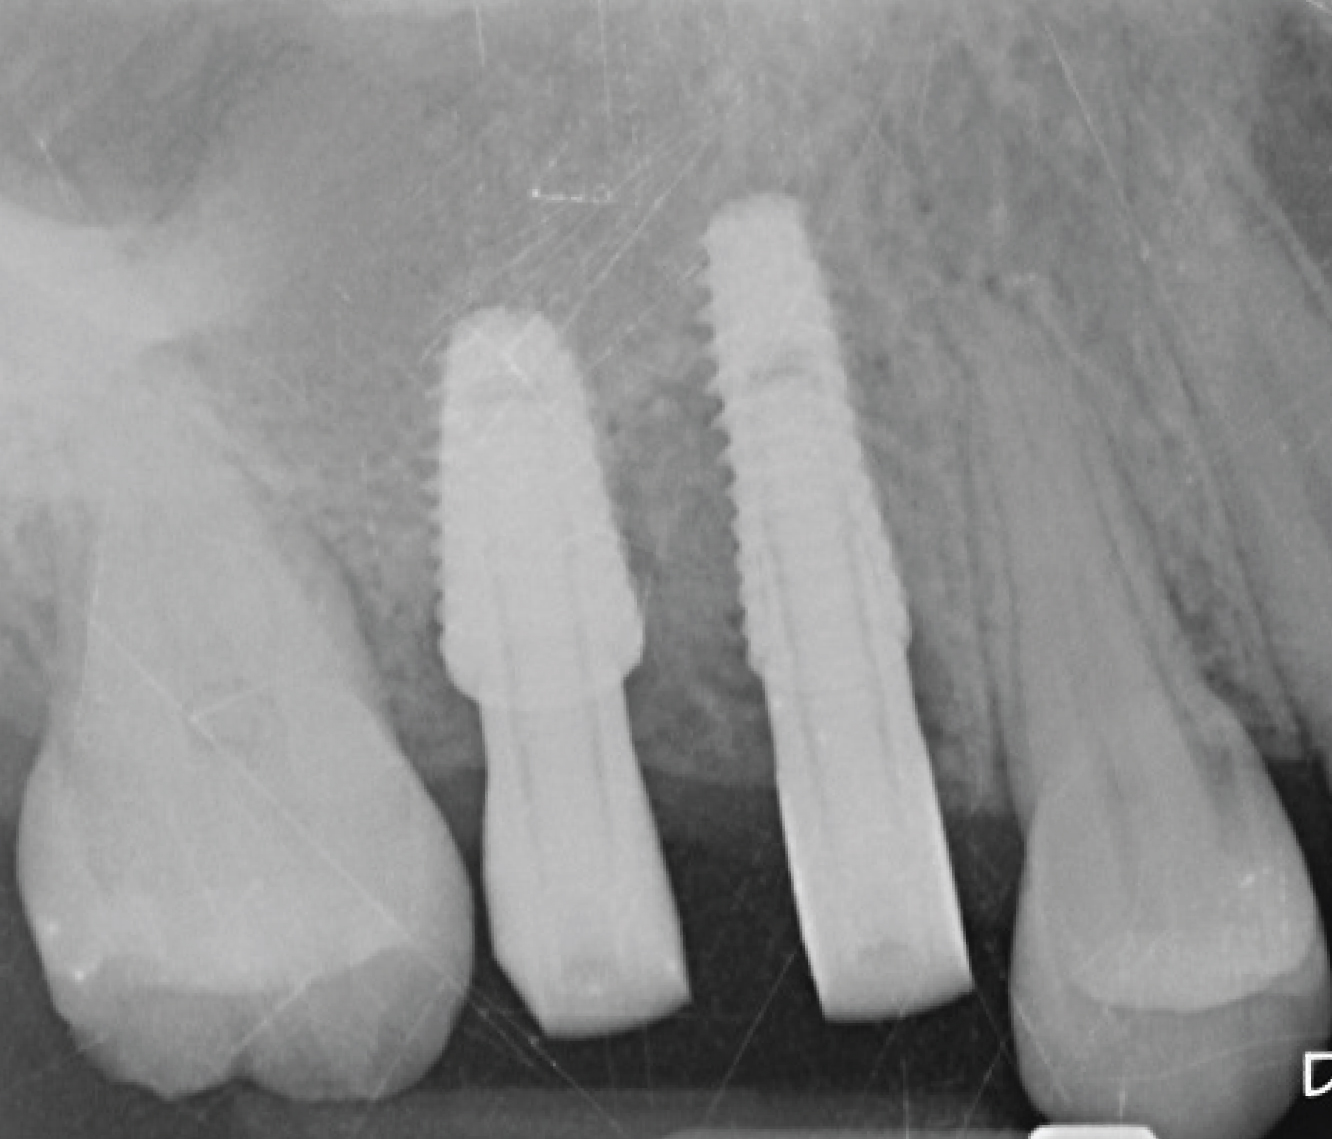

Director’s Clinical Cases

Director’s Clinical Cases